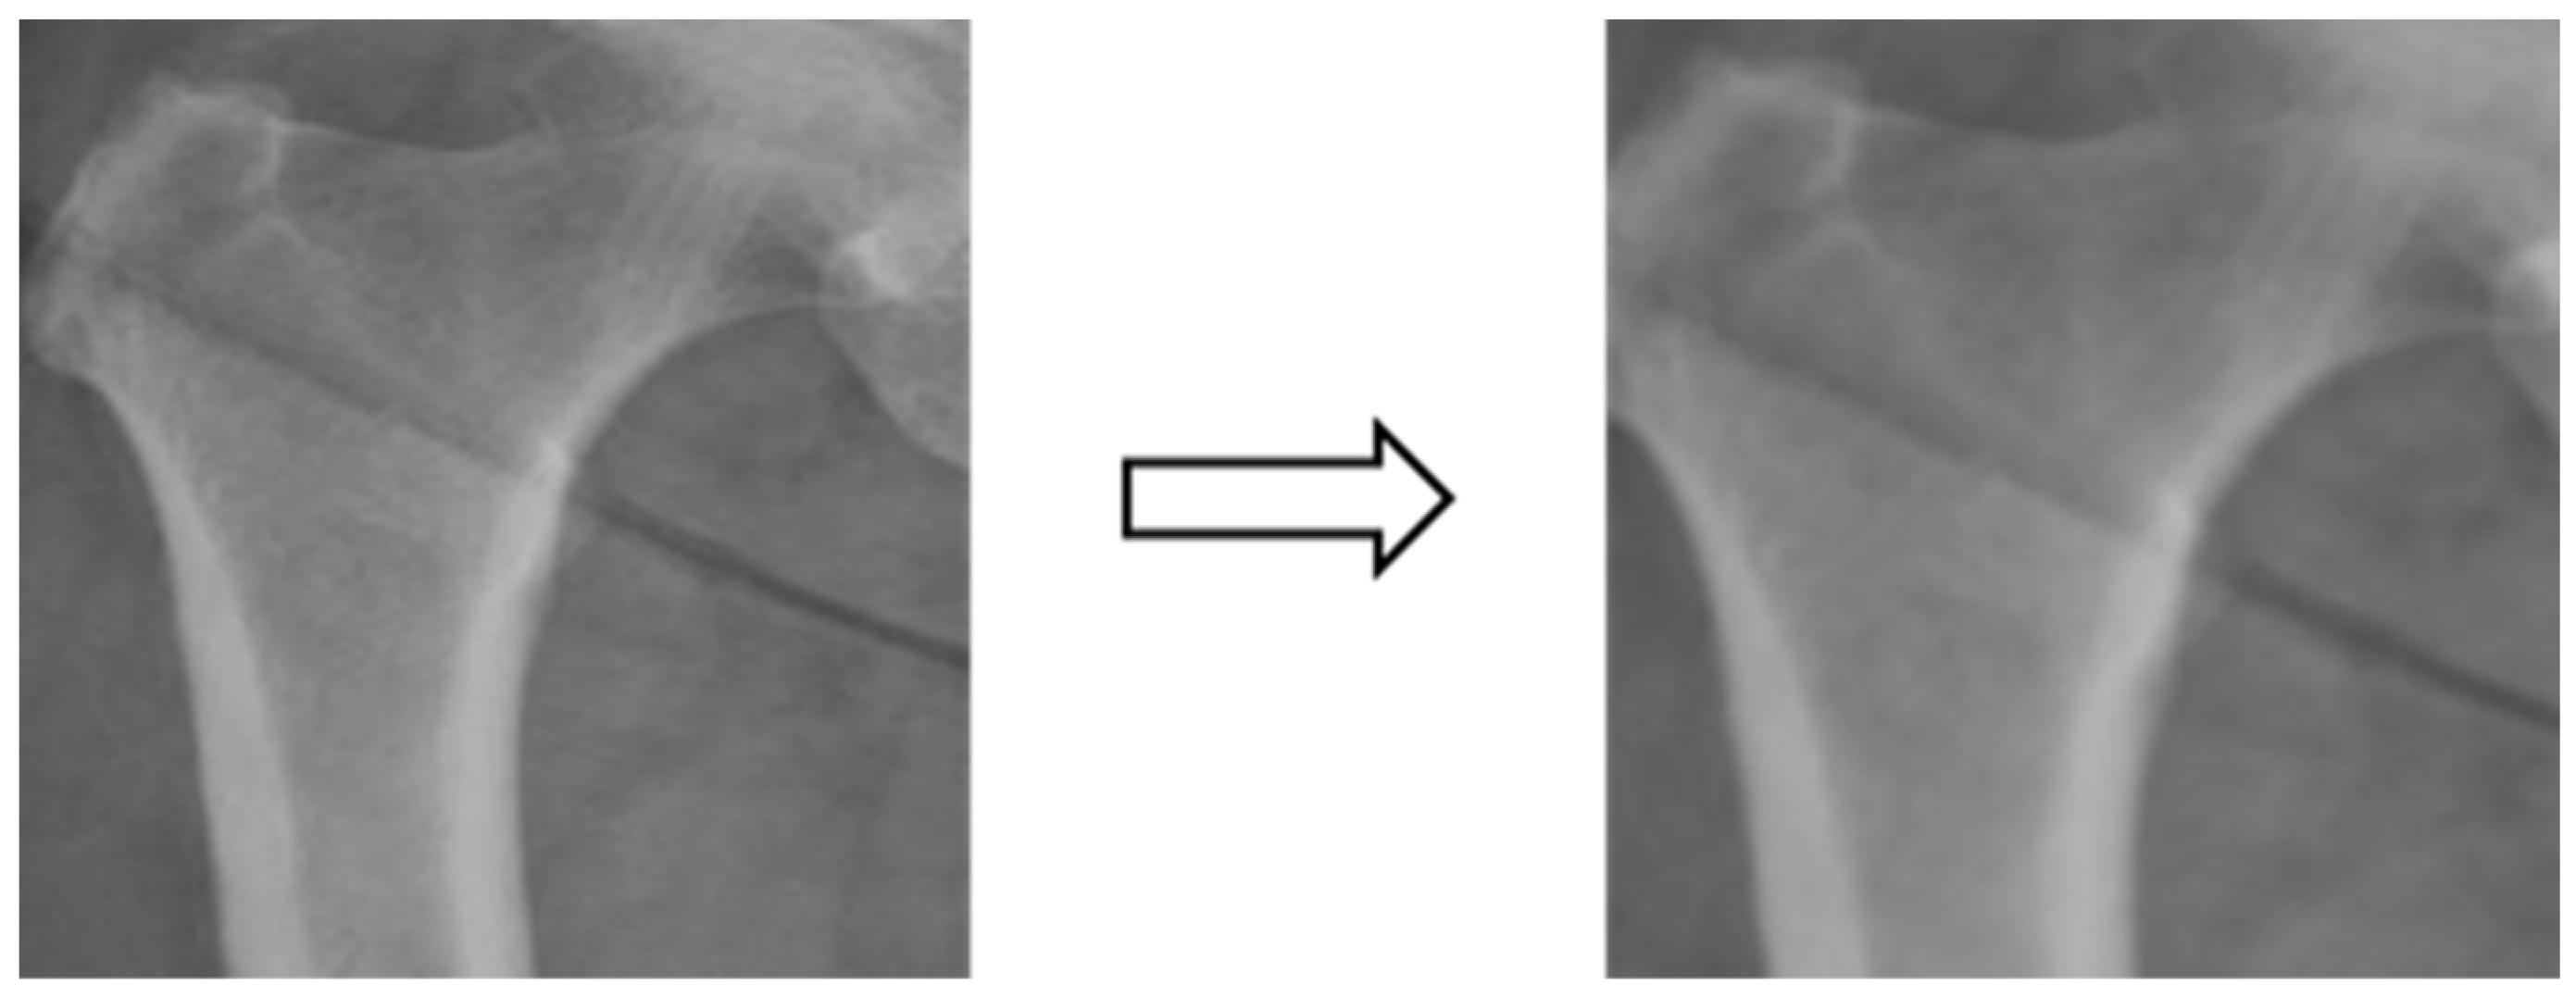

3.3.3. Image Matting

Based on the four parts of the image segmentation of the binary image and the original X-ray image together, the original X-ray image only retains the part of the image segmentation as shown in Figure 4; the other non-part of the contour of the background is removed, and the image is de-behind in the hope that it can enhance the accuracy of the classification of the depth of the learning process, and then the image classification will be segmented images and not segmented images will be compared.

Figure 4.

Image matting.